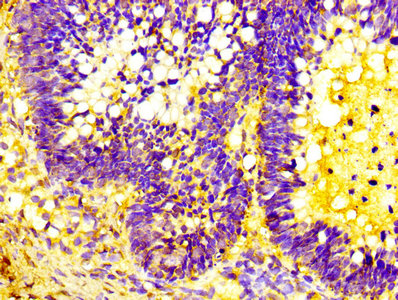

IHC image of CSB-PA10599A0Rb diluted at 1:300 and staining in paraffin-embedded human ovarian cancer performed on a Leica BondTM system. After dewaxing and hydration, antigen retrieval was mediated by high pressure in a citrate buffer (pH 6.0). Section was blocked with 10% normal goat serum 30min at RT. Then primary antibody (1% BSA) was incubated at 4°C overnight. The primary is detected by a biotinylated secondary antibody and visualized using an HRP conjugated SP system.